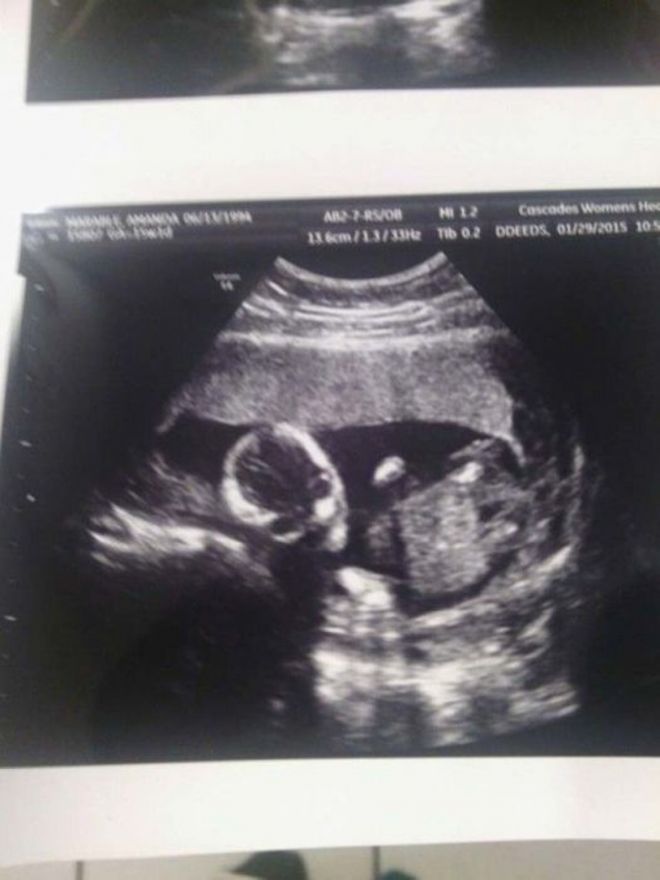

Այսօր ՈՒՁՀ-ն համարվում է հղի կանանց համար ամենակարևոր գործընթացներից մեկը։ Նախ, դրա միջոցով Դուք կարող եք իմանալ՝ այդյո՞ք պտուղը լավ է զարգանում, թե՞ կան որոշակի խնդիրներ։ Երկրորդը՝ հնարավորություն կունենաք տեսնել, թե ինչով է Ձեր փոքրիկը զբաղվում այդտեղ։

ՈՒՁՀ-ն ապագա ծնողների համար ամենահուզիչ պահերից մեկն է, քանի որ նրանք առաջին անգամ ծանոթանում են փոքրիկի հետ։ Պետք է նշել, որ ուլտրաձայնայկն հետազոտության որոշ կադրեր այնքան զվարճալի ու հետաքրքիր են ստացվում, որ ծնողները դրանք հրապարակում են համացանցում։